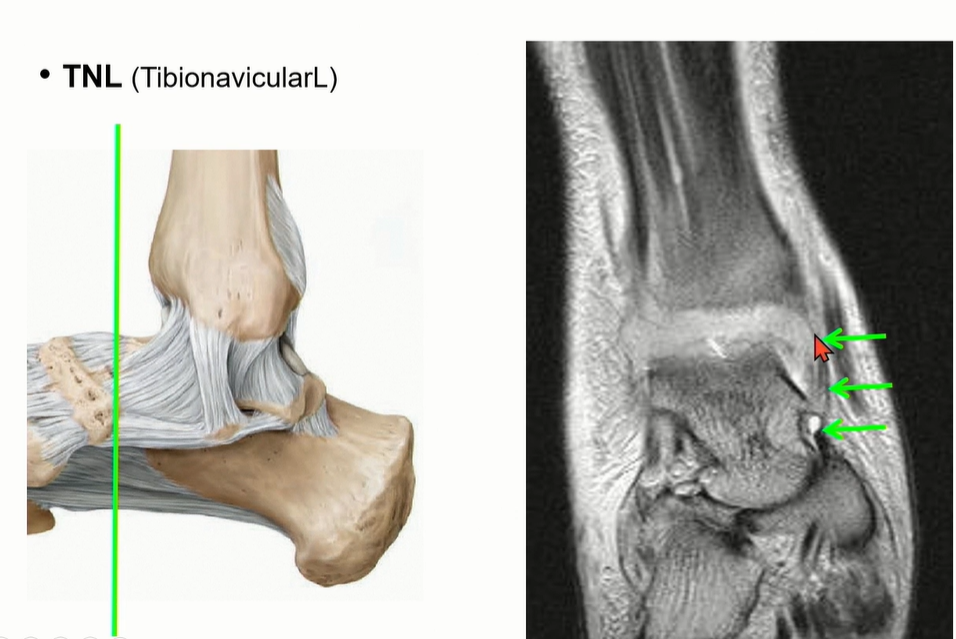

Deltoid ligament의 superficial ligament의 1번에 해당하는 tibionavicular ligement는 주행이 비스듬해서 coronal에서는 잘 관찰이 어렵다. (navicular tuberosity에 붙음)

Deep deltoid liagment의 하나인 PTTL의 주행.